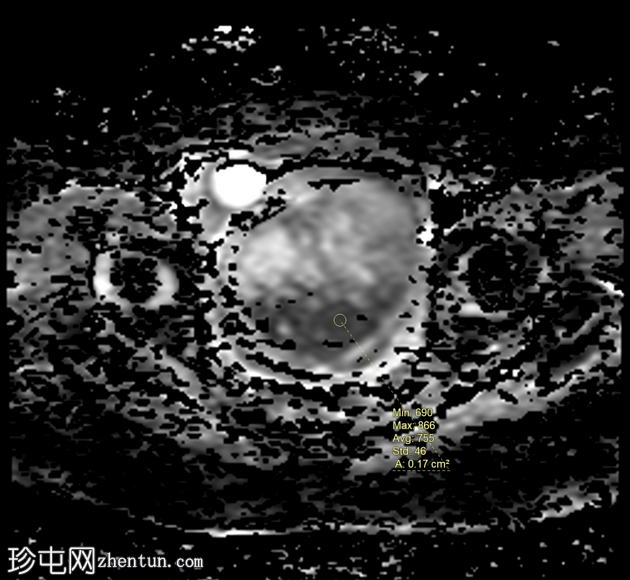

轴位

ADC

病变显示弥散受限区域,DWI信号强度高(等于或高于子宫内膜),实体强化区域ADC映射信号低,测量值小于0.9×10⁻³ mm²/秒(约0.755×10⁻³ mm²/秒)。